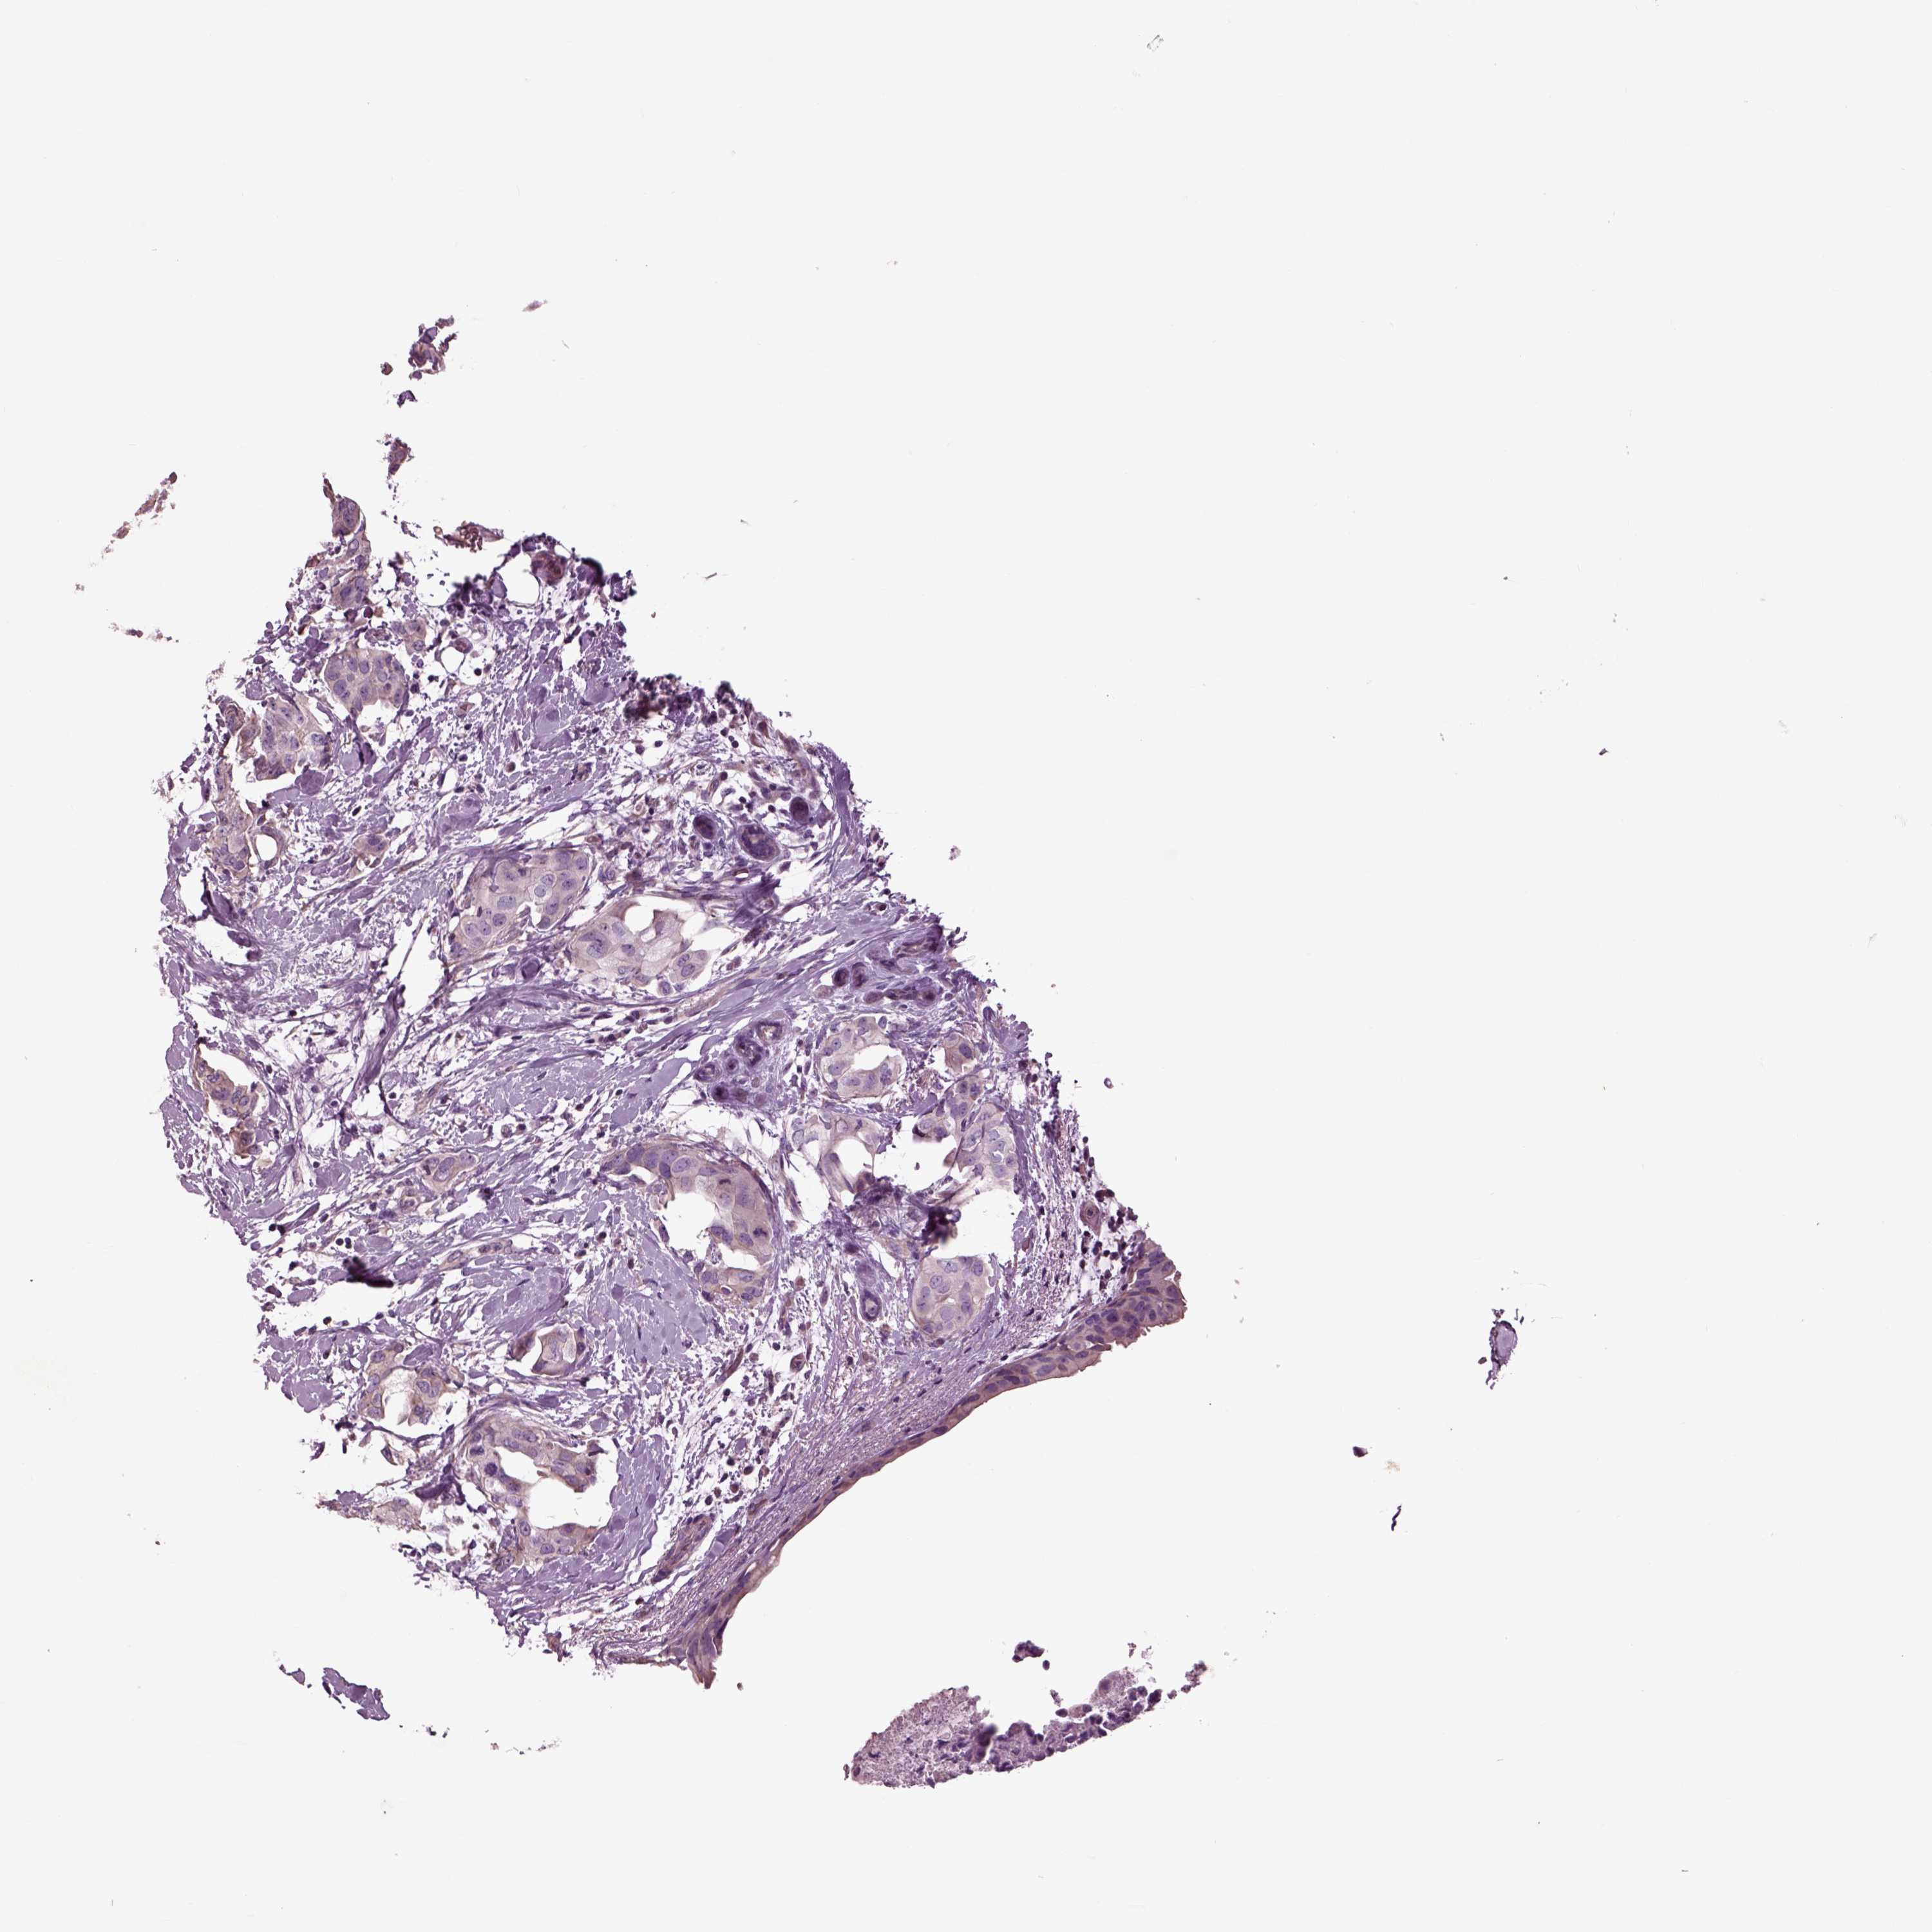

Breast cancer

Human cancer